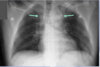

What are the two arrows pointing at? What does the "^" indicate?

* ETT * Central Line